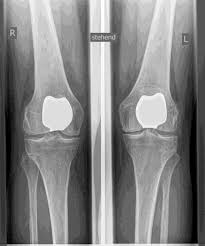

Man spricht bei künstlichen Kniegelenken von Vollprothesen und Teilprothesen. Welche Prothese für Sie in Betracht kommt, Prüfe ich sorgfältig vorher anhand der klinischen Untersuchung, sowie anhand von Röntgenbildern oder MRT-Aufnahmen.

Eine Knie-Totalendoprothese, kurz Knie-TEP, ist ein operativer Eingriff, bei dem die verschlissenen Oberflächen des Kniegelenks durch hochwertige Implantate aus Metall und Kunststoff ersetzt werden. Dieser Gelenkersatz ahmt die natürliche Funktion des Knies nach und ermöglicht wieder einen reibungslosen und schmerzarmen Bewegungsablauf. Ein solcher Eingriff wird in der Regel dann empfohlen, wenn der Gelenkknorpel durch Arthrose (Gonarthrose) so stark geschädigt ist, dass der Patient unter dauerhaften Schmerzen, Bewegungseinschränkungen und einem Verlust an Lebensqualität leidet.

Das künstliche Kniegelenk ersetzt die durch die Arthrose zerstörte Knorpeloberfläche. Der darunterliegende Knochen am Oberschenkel und Schienbeinkopf bleibt erhalten. Manche vergleichen ein modernes künstliches Kniegelenk mit einer

Überkronung bei einem Zahn, der genaue Begriff ist der sogenannte

bikondyläre Oberflächenersatz. Zwischen den neuen Oberflächen am Ober- und Unterschenkel befindet sich das sogenannte Inlay aus einem speziell verhärteten weißen Kunststoff, das im Röntgenbild als Abstand zwischen den Metallteilen zu erkennen ist.